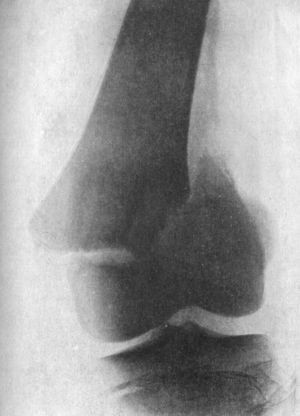

86 36.Backward Dislocation of Elbow in a Boy

89 37.Bony Outgrowth in relation to insertion of Brachialis Muscle